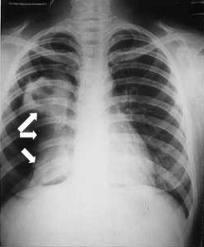

El causante de esta enfermedad infecciosa es la bacteria Mycobacterium tuberculosis, un organismo que casi siempre afecta a los pulmones. La afección es curable y se puede prevenir. La transmisión persona a persona se produce a través del aire, en la tos, estornudo o cuando alguien escupe. Curiosamente, una tercera parte de la población mundial está infectada de forma asintomática, latente. Durante dicho periodo, no se transmite la infección. El riesgo de enfermar, una vez infectada una persona, a lo largo de su vida, es del 10%.